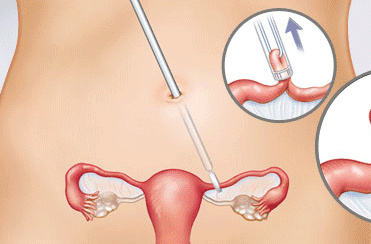

قیمت: 42٬000 تومان - دسته بندی فایل: پاورپوینتپاورپوینت روش های بستن لوله

فروش ویژه پاور پوینت حرفه ای روش های بستن لوله با تخفیف استثنایی فقط 29 هزار تومان تعداد اسلاید: 17 اسلاید